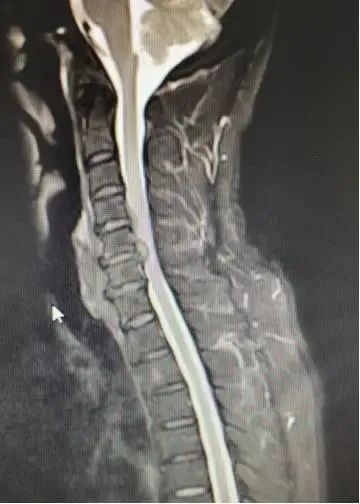

After the patient was admitted to the hospital, relevant examinations were carried out. Director Chen Fangtian examined the patient’s condition in detail and said: The patient presented with cervical disc herniation (C4/5, C5/6), cervical spinal canal stenosis (C5/6). ), and symptoms of spinal cord and nerve compression. The diagnosis was clear, non-surgical treatment is ineffective, the patient has clear indications for surgery and has no obvious contraindications to surgery, therefore surgical treatment can be considered.

1733282388 1 3D Printed Porous Vertebral Body Cage Successfully Used in Anterior

△Patient preoperative imaging data